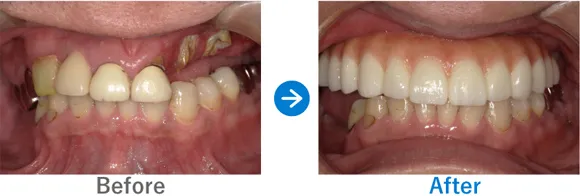

Case13

強いブラキシズムで削れた歯に悩める女性が、インプラントでとびっきりの笑顔に!

ブラキシズムがあり、咬合力が強く、順番に歯が破折

インプラント9本:右下6、左下6(2015年)、右下7、左下7、左上3・4、抜歯ソケットプリザベーション、左上3・4・5(2025年)

7,224,760円(内訳:インプラント2本(ノーベル)、抜歯、保証10年(2015年)/インプラント7本(ストローマン)、サイナスリフト、セデーション、ガイド、仮歯、補綴治療、ボツリヌストキシン注射、保証20年(2025年))

来院の背景

ブラキシズム(無意識下の歯ぎしり、食いしばりなど)が強く、10年前に下顎左右の奥歯が割れてインプラントにした方です。ブラキシズムにより歯が全体的に削れている状態で、破折している歯は抜歯が必要でした。歯の短さが気になり、笑顔になれないとお悩みだったため、。噛み合わせの観点からも、破折した歯をインプラントにするだけでなく、全体的に咬合治療が必要であることを説明し、全顎の補綴治療を提案しました。

治療結果

強いブラキシズムの影響で歯の咬耗が激しく、破折もみられました。破折した歯は抜歯しインプラント治療を行い、全顎の補綴治療を行いました。

治療過程では、ブラキシズムにより調整期間中の仮歯が何度も壊れてしまい、涙を流されることもありました。マウスピースとボツリヌストキシン注射でブラキシズム対策をしながら治療が完了。噛み合わせはもちろん、審美的にも整いとても喜ばれていました。今後も引き続きマウスピースやボツリヌストキシン注射でブラキシズム対策を行っていくことが大切です。